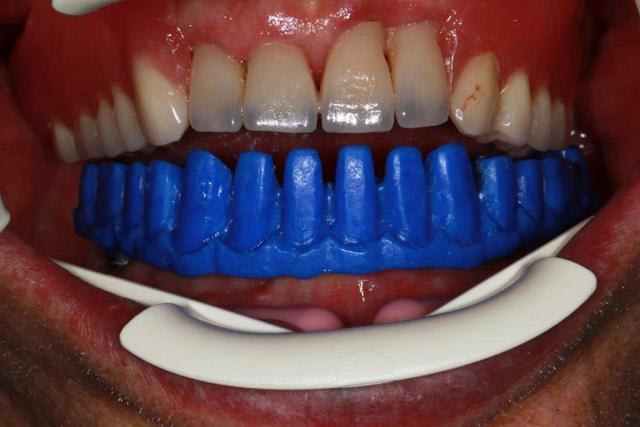

cicatrisation à 8 jours...ras donc ce sera implants pour le bas.

En flapless

empreinte, et fabrication de l'armature métal

Dans le même temps essayage pour le haut